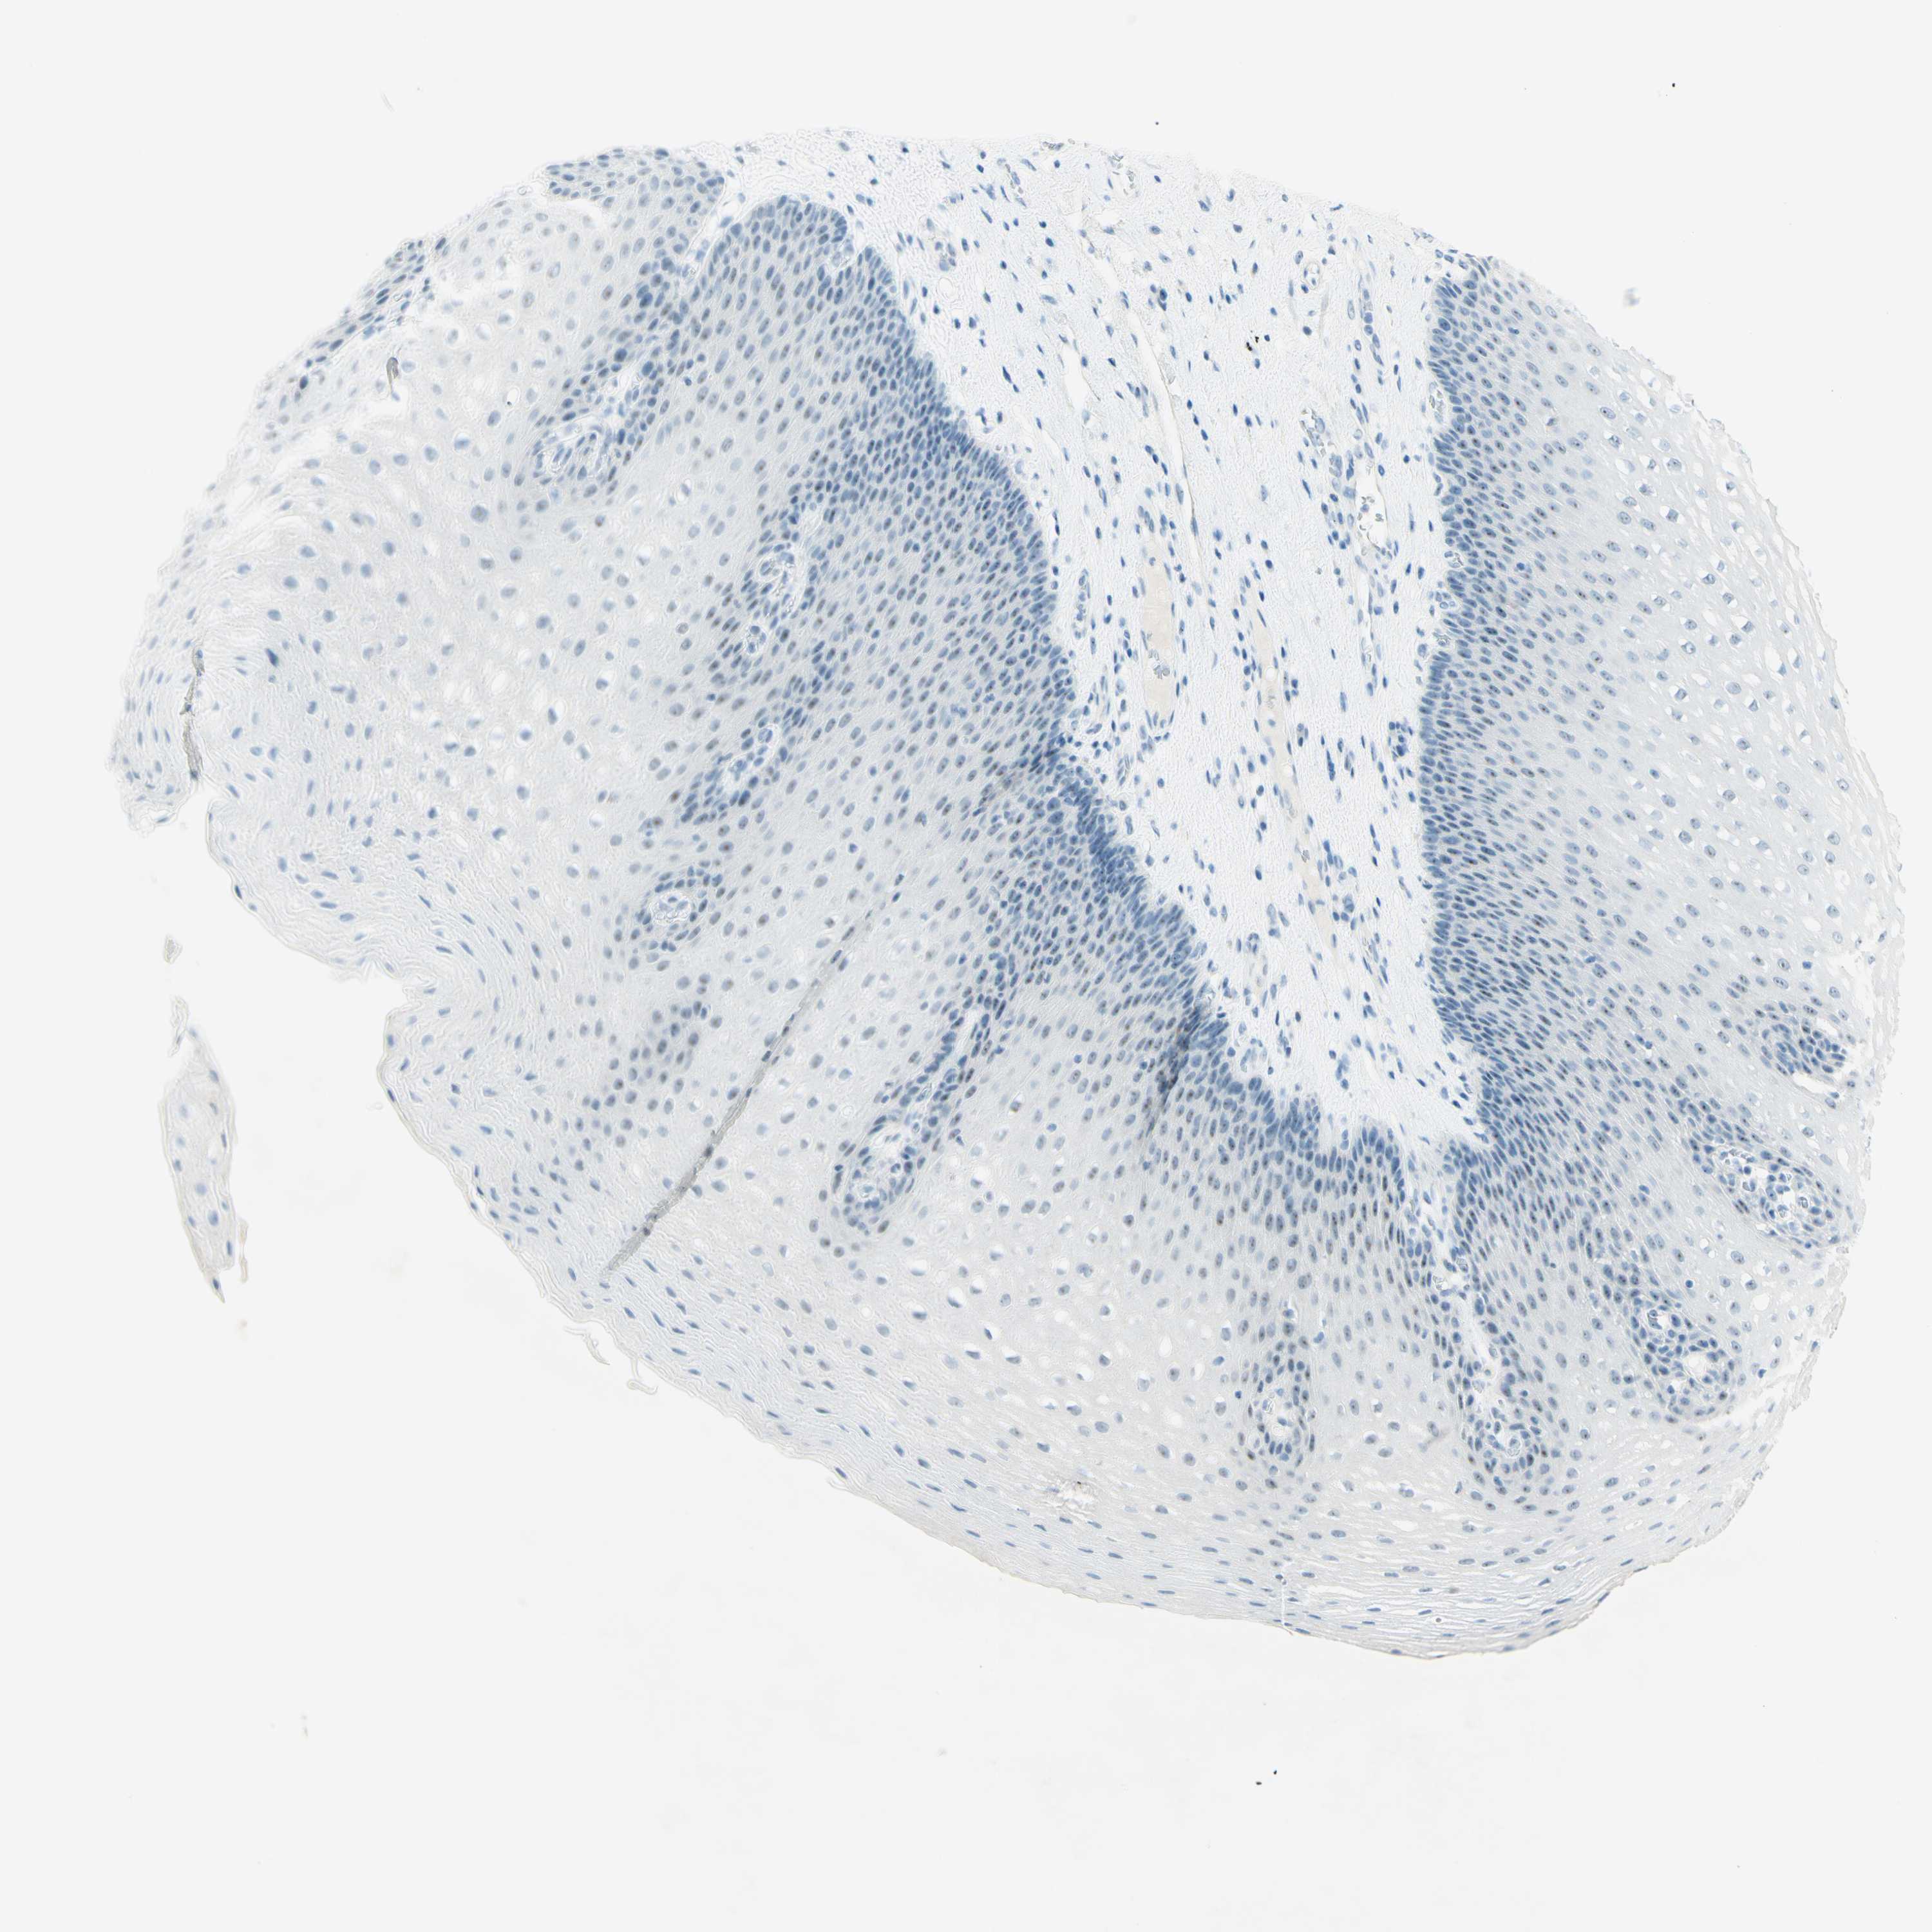

ESOPHAGUS - Antibody stainingi

Antibody staining in the annotated cell types in the current human tissue is reported as not detected, low, medium, or high, based on conventional immunohistochemistry profiling in selected tissues. This score is based on the combination of the staining intensity and fraction of stained cells.

Each image is clickable and will lead to virtual microscopy that enables deeper exploration of all samples and also displays staining intensity scores, fraction scores and subcellular localization as well as patient and tissue information for each sample.

Antibody HPA011284Antibody CAB026403

Squamous epithelial cells Not detectedNot detected